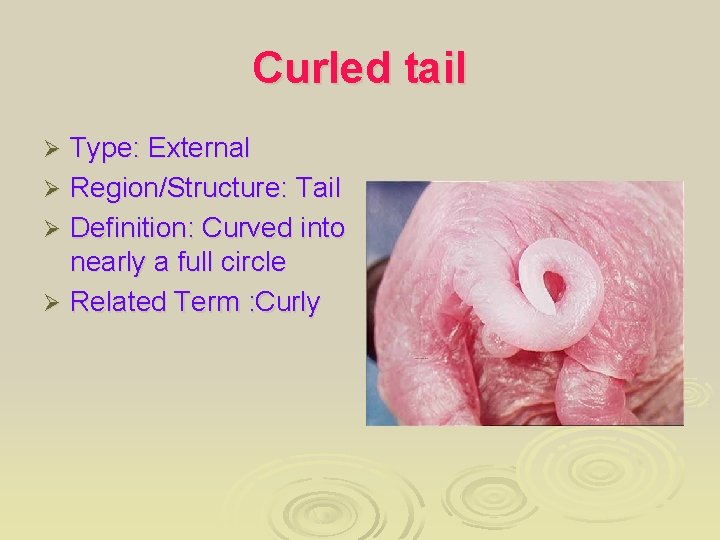

Curled tail Type: External Ø Region/Structure: Tail Ø Definition: Curved into nearly a full circle Ø Related Term : Curly Ø